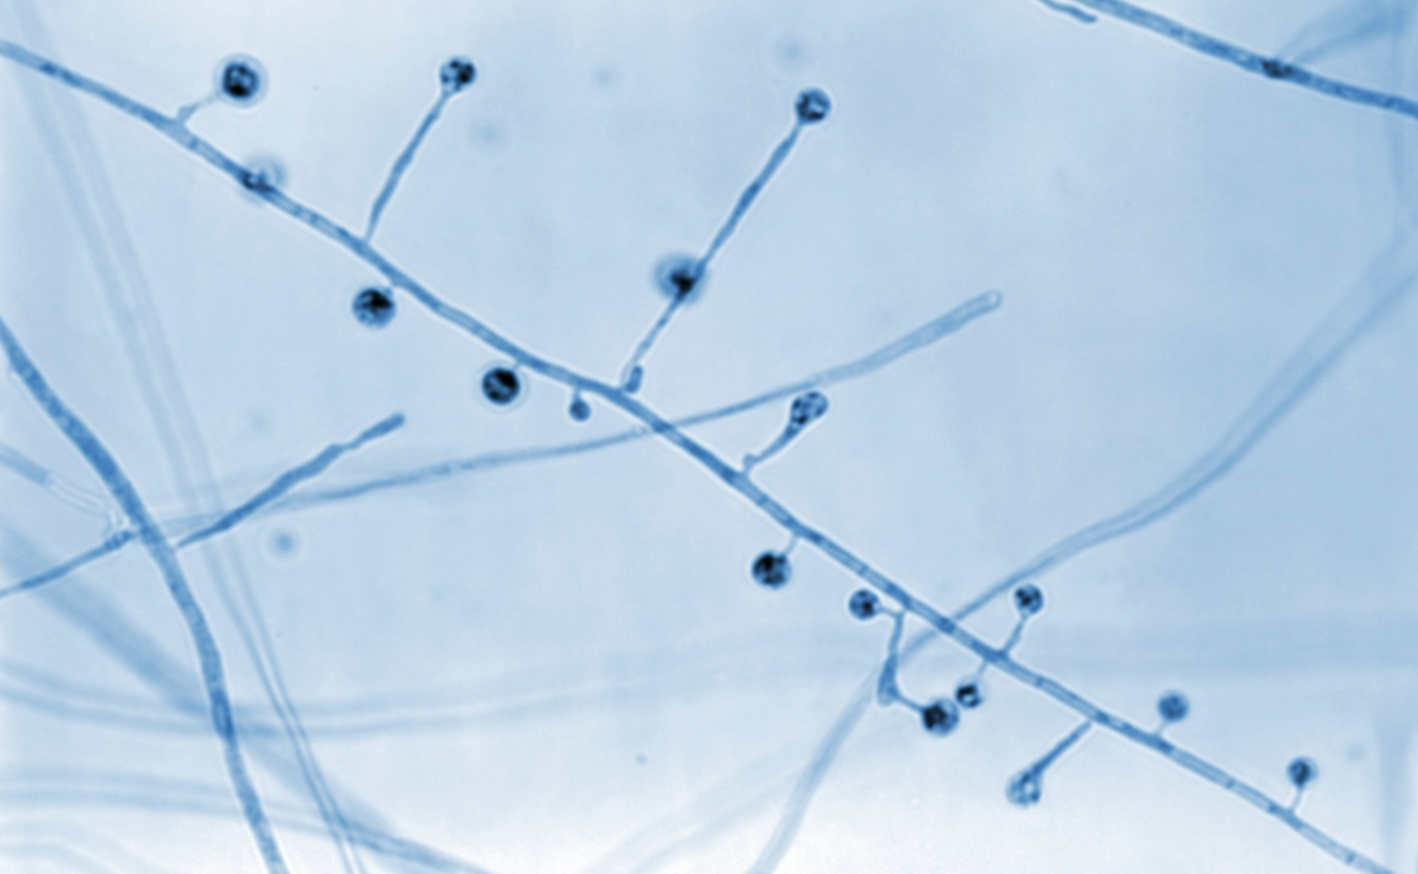

| Sporothrix schenckii |

Culture (25ºC): branching hyphae. Biopsy: round or cigar-shaped budding yeasts. |